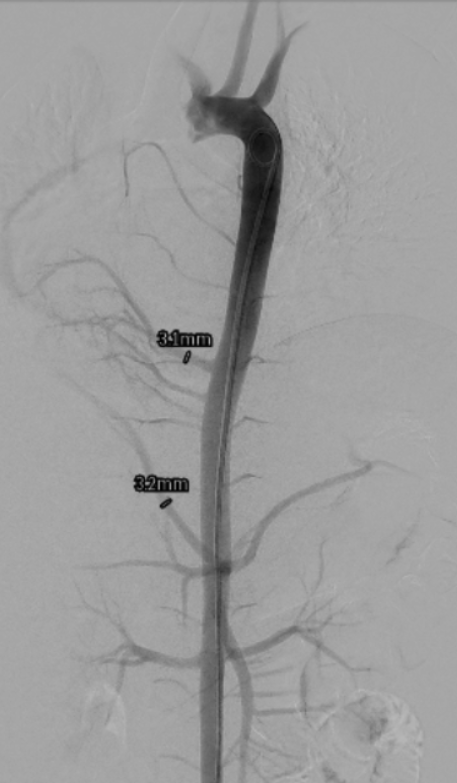

Following resolution of pneumonia, the child underwent cardiac catheterization, which confirmed dual arterial supply to the right lung via the right pulmonary artery and APCs. It was decided to redirect flow and reduce shunting using vascular plugs. First, femoral access was obtained with a 5F catheter. Next, a digital subtraction aortogram was performed with a 5F pigtail catheter. The prominent APC from the DTA measured 3.1 mm; it was hooked with a 5F Judkins right (JR) guiding catheter. A 4 x 6-mm Amplatzer Vascular Plug II (Abbott) was then deployed into the APC under angiographic guidance. The APC from the celiac artery measured 3.2 mm; it was hooked with a 5F JR guiding catheter. A 6 x 6-mm Amplatzer Vascular Plug II was deployed into the APC under angiographic guidance. The prominent APCs were successfully occluded (Figure 3), and post-deployment angiogram showed good position and good flows in the celiac artery and its other branches (Video 2).